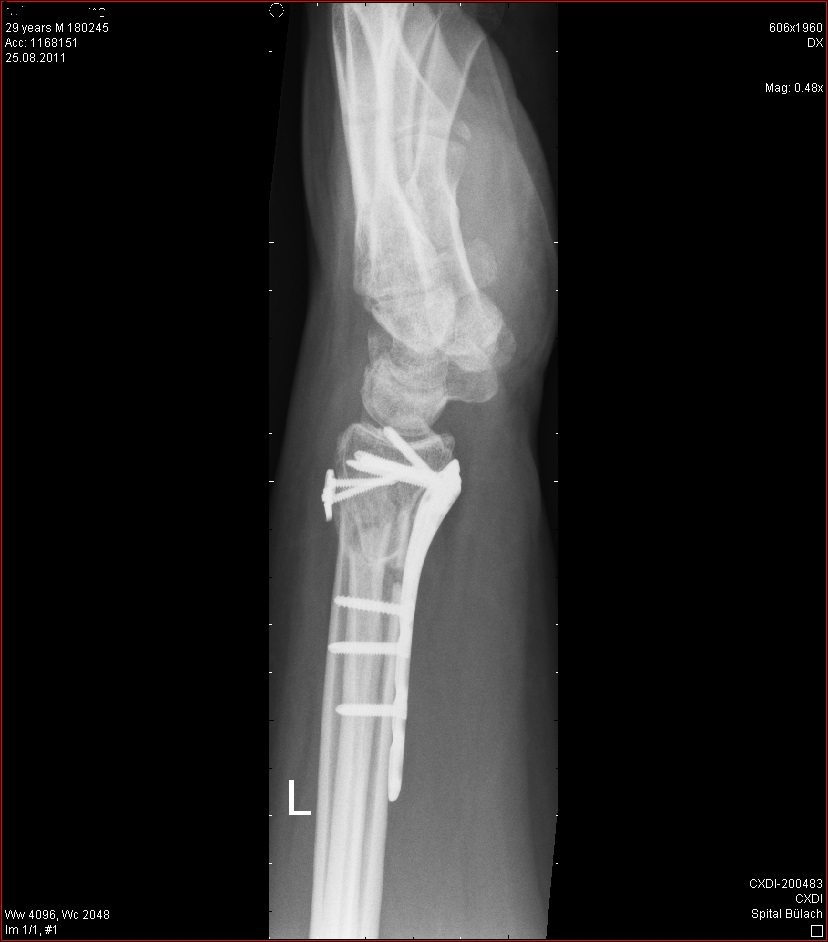

Die erste OP dann mit 18. Die zweite mit 22 und die letzte im Dezember 2013.